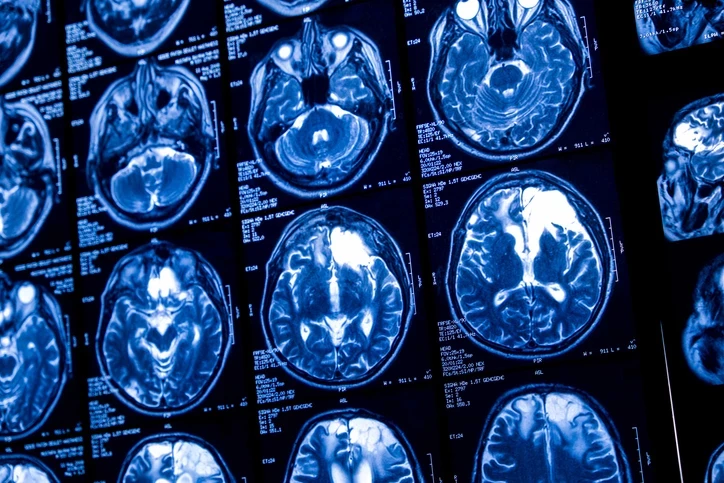

Tıpta görülmemiş vaka: Beyninden canlı solucan çıktı! ( 7 / 9 )

Araştırmacılar kadının göl kenarındaki evinin çevresinde pitonların yaygın olduğunu, sık sık doğadan yabani ot toplayarak yemek yaptığı için parazitin yumurtalarıyla kirlenmiş bitkilere temas etmiş veya onları tüketmiş olabileceğini düşünüyor. Yumurtaların vücuda girdikten sonra açıldığı ve larvaların akciğer, karaciğer ve en sonunda beyne kadar göç ettiği değerlendiriliyor.

Tıpta görülmemiş vaka: Beyninden canlı solucan çıktı!